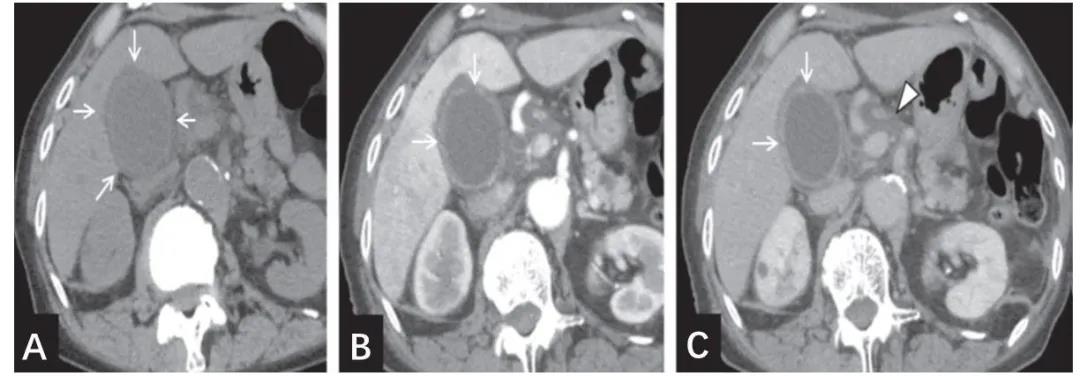

图3 典型的坏疽性胆囊炎CT图像(A平扫,B增强早期,C增强平衡期)。

CT平扫图像上可清楚显示胆囊体积增大、胆囊壁增厚及浆膜下水肿性病变。增强CT图像(B、C)上可见坏疽性胆囊炎的特征性表现:胆囊壁不规则及部分胆囊壁未强化。一过性肝实质早期强化(B)及肝十二指肠韧带水肿(C)提示炎症扩散。